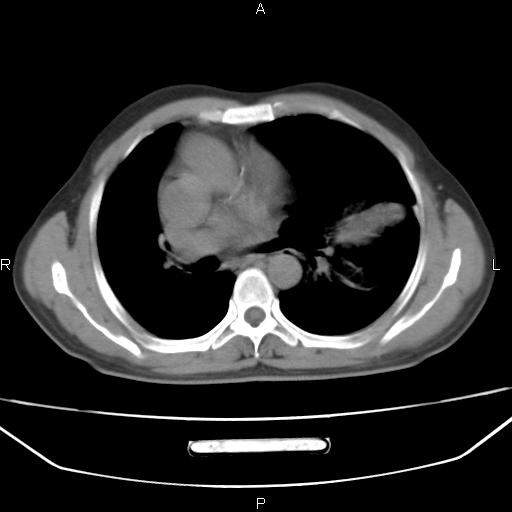

患者,男。50岁。近几日有咳嗽症状,无其他不适,既往病史无,考虑膈疝。请前辈们看看指导指导。

膈膨升,左下肺通气不良,膈肌好像还完整。

考虑左侧膈疝。

左侧膈疝。

符合隔膨升,膈肌较完整。